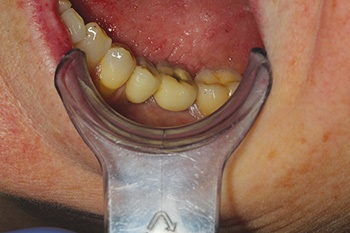

Fig. 2: Pre-op occlusion.

Frances was seen by my colleague, a prosthodontist, who treatment-planned her to have the premolar removed and a single implant placed into the molar site. That implant would then be used to support a cantilever bridge, replacing both the molar and premolar teeth.

So, I placed an 8 mm-long Ankylos implant into her lower left first molar site. Three months later, the prosthodontist restored it with a cantilever bridge.